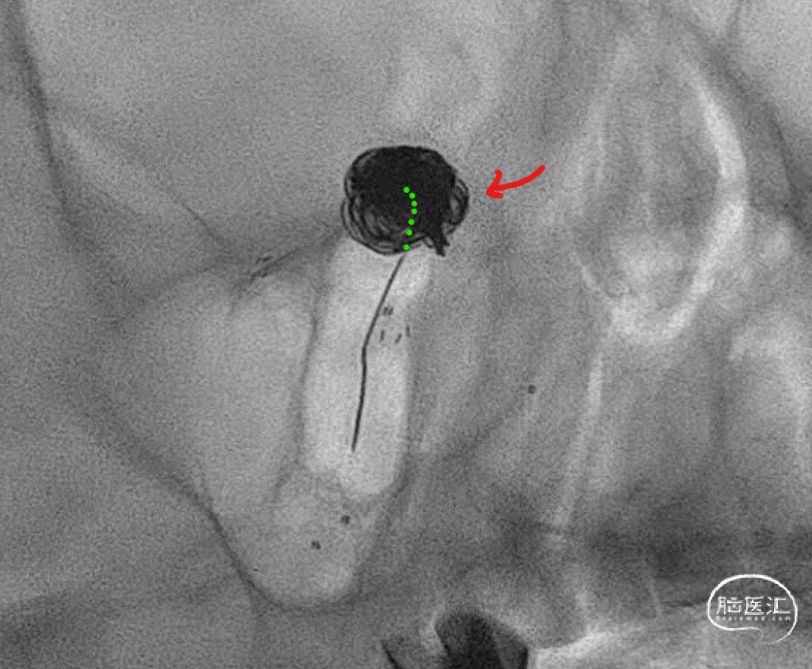

这个角度,感觉残留一些。

换了个角度,感觉还可以。

标准侧位发现,这个位置有些残留,角度还是比较刁的,不太好到位。虽然有这么一点小遗憾。但是从患者是未破裂动脉瘤,及减少患者风险为第一位的角度上看,还是可以考虑一下。因此毅然决定收手。术后患者安好。

静下来想想,有的时候我们追求完美,让手术和患者得到最大的受益无可厚非。但是有的时候能及时收手,减少患者由于增加操作而带来的风险,未尝不是一种正确的选择。仅为个人观点,与诸君分享。同时感谢各位关注。